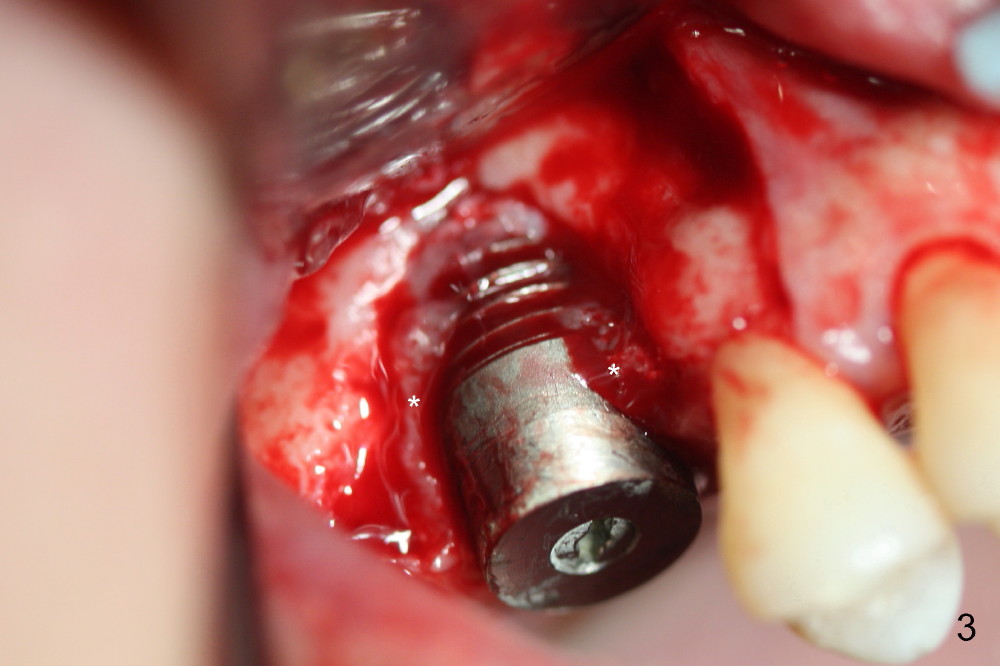

The surgery is finished as planned. Fig.2,3 (intraop photos) show thread exposure. The fistula is closed with perio glue. The defect appears to be a preexisting condition. Bone graft may be not enough or get infected. Or the implant is oversized, or placed too buccally (because of palatal defect).